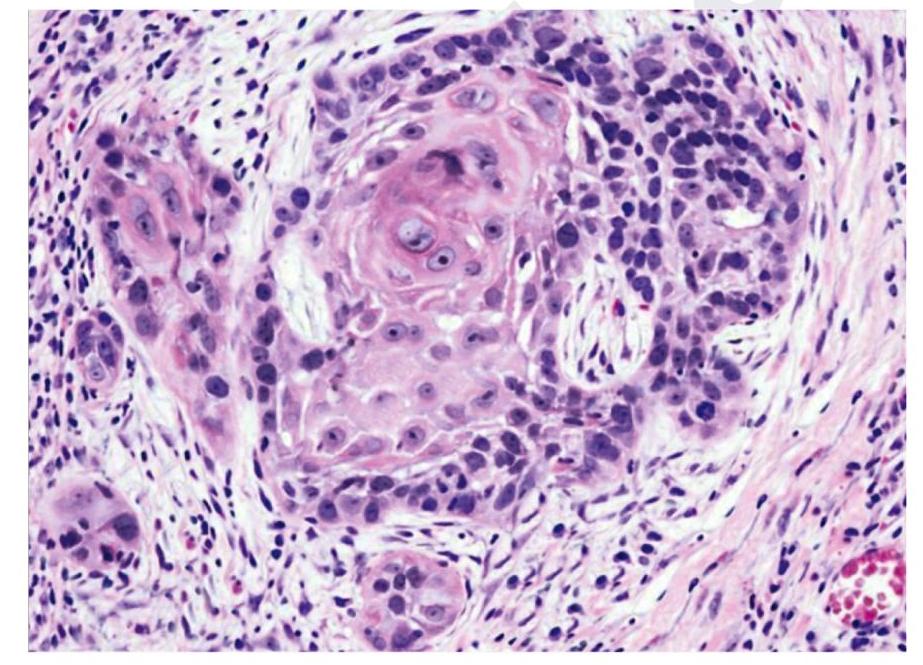

A male patient with hemoptysis. On examination, hilar mass was present. The histopathological image is shown below. Immunohistochemistry revealed that the cells were positive for p40. What is the diagnosis?

Explanation: ***Squamous cell carcinoma*** - The image displays features characteristic of **squamous cell carcinoma**, including nests of polygonal cells, prominent nucleoli, and areas of **keratinization** (forming keratin pearls) which are indicative of squamous differentiation [1]. - The positive immunohistochemistry staining for **p40** is a highly specific marker for squamous cell differentiation, further confirming the diagnosis in the context of a hilar mass and hemoptysis, which are common presentations for this type of lung cancer [2]. *Adenocarcinoma lung* - **Adenocarcinoma lung** typically presents with glandular differentiation, featuring structures like acini, tubules, or papillae, and often produces mucin, none of which are evident in the provided image [1]. - Immunohistochemically, adenocarcinoma would typically stain positive for **TTF-1** or **Napsin A**, and would be negative for p40. *Small cell carcinoma* - **Small cell carcinoma** shows small, round to oval cells with scant cytoplasm, finely granular chromatin (salt and pepper pattern), and frequent mitoses with extensive necrosis [3]. - These cells are much smaller than squamous cells and lack keratinization. IHC would show positivity for **synaptophysin, chromogranin, and CD56** (neuroendocrine markers), not p40 [3]. *Large cell carcinoma* - **Large cell carcinoma** is a diagnosis of exclusion showing undifferentiated large cells without glandular or squamous differentiation features. - It lacks the keratinization and intercellular bridges seen here, and would be **p40 negative** as it shows no squamous differentiation. **References:** [1] Kumar V, Abbas AK, et al.. Robbins and Cotran Pathologic Basis of Disease. 9th ed. The Lung, pp. 723-724. [2] Cross SS. Underwood's Pathology: A Clinical Approach. 6th ed. Common Clinical Problems From Respiratory Tract Disease, pp. 336-337. [3] Cross SS. Underwood's Pathology: A Clinical Approach. 6th ed. Common Clinical Problems From Respiratory Tract Disease, pp. 337-338.